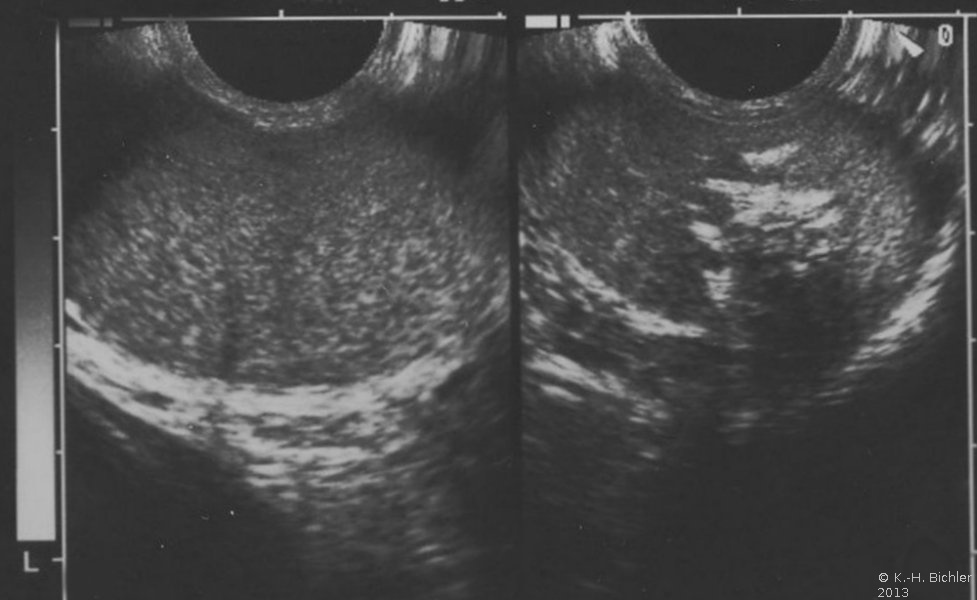

Die Hodenfreilegung und Schnellschnittuntersuchung zeigten ein embryonales Karzinom mit Seminoma in situ. Im Orchidektomiepräparat fand sich ein umschriebener, inhomogener Tumor mit Einblutungen (Abbildung 4).